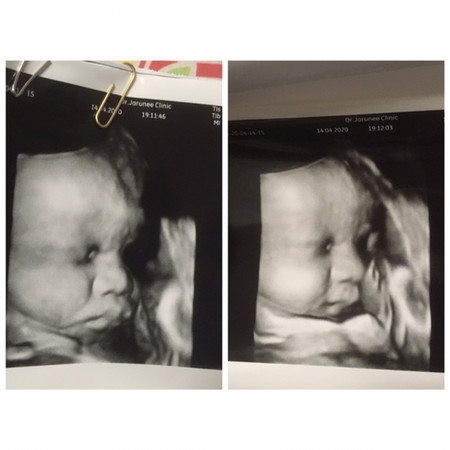

34 W

อยากเจอหน้าแล้วลูกชาย